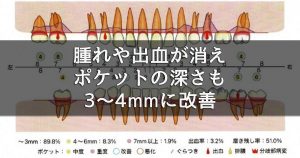

歯周病治療3週間集中プログラムの症例紹介 60代男性 T様のケースをご紹介いたします。 治療1カ月後は、腫れや出血が消え、ポケット深さも3〜4mmに改善。就寝時に口の中…